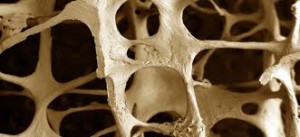

Η οστεοπενία είναι η λέπτυνση της οστικής μάζας. Ενώ αυτή η μείωση στην οστική μάζα δεν θεωρείται συνήθως σοβαρή, αποτελεί ένα πολύ σοβαρό παράγοντα κινδύνου για την ανάπτυξη της οστεοπόρωσης.

Η οστεοπενία είναι κάτι συνηθισμένο σε άτομα άνω των 50 ετών που έχουν χαμηλότερη από το μέσο όρο οστική πυκνότητα, αλλά δεν έχουν οστεοπόρωση. Η διαγνωστική διαφορά μεταξύ οστεοπενίας και οστεοπόρωσης είναι το ποσοστό της οστικής πυκνότητας.

Η οστεοπόρωση είναι μια πάθηση που χαρακτηρίζεται από μειωμένη οστική πυκνότητα, μειώνεται η δύναμη του οστού και οδηγεί σε αυξημένη ευθραυστότητα, και συνεπώς σε αυξημένο κίνδυνο κατάγματος. Η απώλεια της οστικής μάζας προκαλείται από μια ανεπάρκεια σε ασβέστιο, βιταμίνη D, μαγνήσιο και σε άλλες βιταμίνες και μέταλλα. Πολλά από τα τρόφιμα που τρώμε περιέχουν αυτές τις βιταμίνες και τα μέταλλα “οικοδόμησης” των οστών.